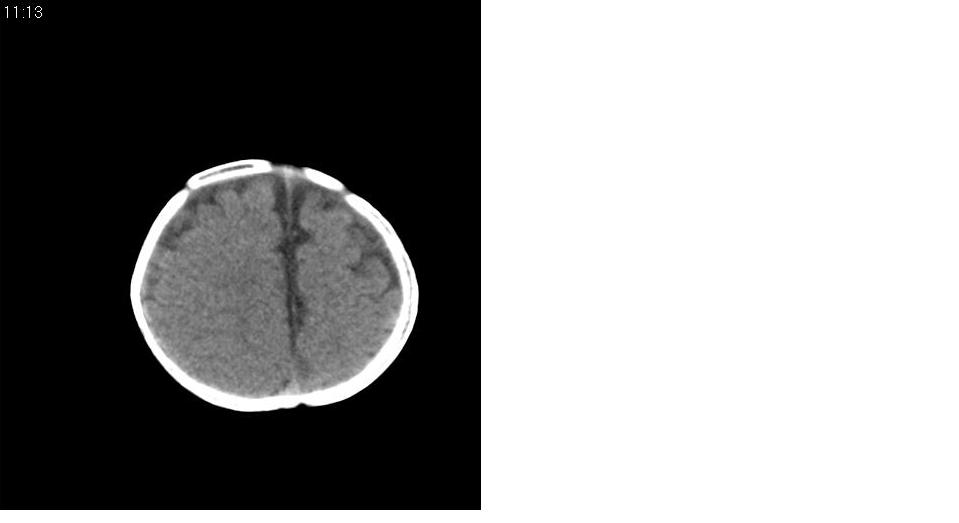

标题: PED1744:颅脑CT平扫

男 3个月,头大,颈软,头向后仰。

外部性脑积水

考虑外部性脑积水。

脑外间隙增宽,未见明显异常。

脑外间隙增宽,余未见明显异常。

脑外间隙增宽,现在好像有人说是一种发育性的交通性脑积水

蛛网膜增宽,外部性脑积水?

外部性脑积水(也就是诸位说的脑外间隙增宽);脑实质内未见异常密度灶,脑室系统无扩张,建议随访,毕竟临床症状听着怪吓人的。